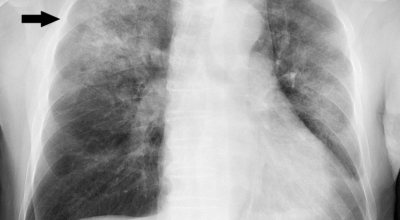

인체가 순조롭게 기능을 발휘하려면 폐 건강이 필수다. 폐는 인체가 효율적으로 움직이는 데 있어 바퀴 안에 있는 톱니 같은 역할을 하기 때문이예요. 산소를 제공하는 폐 기능이 감소하게되면 폐렴이나, 만성 폐쇄성 폐질환(COPD), 천식 등 정도가 심한 호흡기 질환 발생 위험이 증가해요. 이런 질병들은 폐를 공격해 숨쉬기 힘들게 만들어요.

특별히 현대 사회에서 폐는 가장 시달리는 장기 중 한 종류다. 가지가지 공해 성분으로 오염된 공기에 미세 먼지, 황사까지 더하면 폐 안쪽에 있는 허파꽈리(폐포)부터 정도가 심한 훼손을 입습니다. 따라서 폐 건강을 증진시키기 위하여는 폐에 좋은 음식을 섭취할 필요가 있어요.